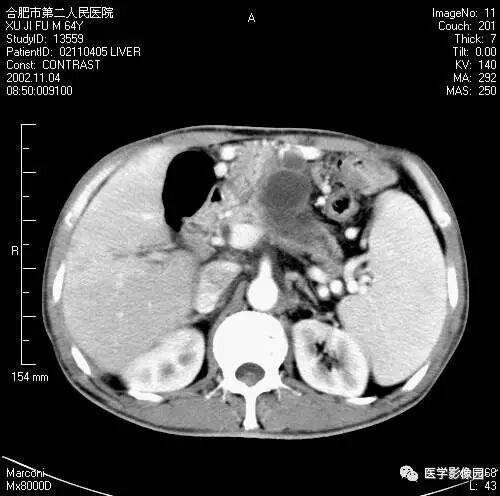

图6-4-16胰腺癌

A. 增强扫描见胆总管扩张(↑),

胆囊扩大,左肾有两个小囊肿;

B.(与A图间隔5mm的层面)扩张的总胆管

突然中断、消失,钩突部见低密度肿块